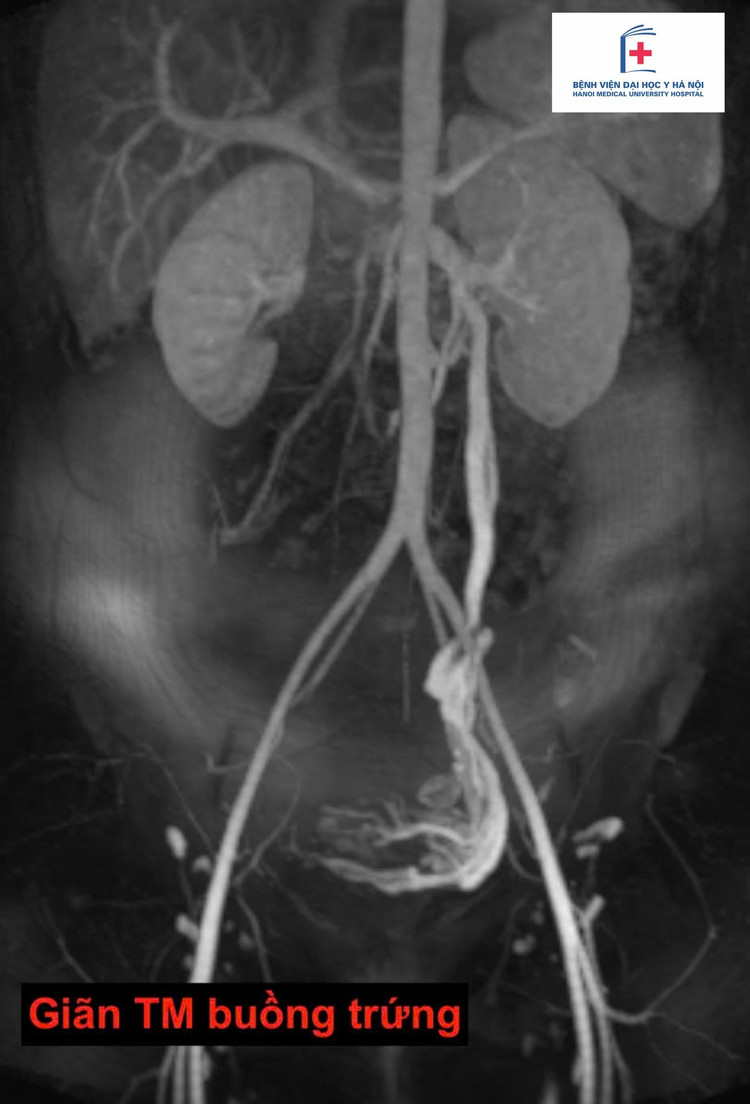

TS.BS Nguyễn Ngọc Cương, Trưởng khoa Điện quang can thiệp, Bệnh viện Đại học Y Hà Nội cho biết, hội chứng xung huyết vùng chậu thường gặp ở phụ nữ trung niên, đặc biệt ở những người đã từng sinh con.

Triệu chứng điển hình là đau âm ỉ vùng bụng dưới kéo dài, thường lệch trái, đau tăng khi đứng lâu, đi lại nhiều, hoặc vào cuối ngày. Một số trường hợp kèm cảm giác nặng vùng tiểu khung, rối loạn tiểu tiện nhẹ, hoặc khó chịu khi quan hệ.

Do không có dấu hiệu rõ ràng và dễ nhầm lẫn với các bệnh lý tiêu hóa, phụ khoa hay tiết niệu nên hội chứng xung huyết vùng chậu dễ bị bỏ sót nếu không được thăm khám đúng chuyên khoa.